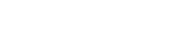

Chez le cheval, les tendons fréquemment sujets au développement de foyers dégénératifs sont par exemple le suspenseur du boulet et le tendon fléchisseur profond (photos 1 et 2). Chez le chien, le tendon d’Achille (ou corde du jarret) (photo 3) et le fléchisseur ulnaire du carpe (photo 6) sont parfois sujets à une pathologie chronique.

Image échographique en vue longitudinale de l’insertion proximale du suspenseur du boulet chez un cheval présentant une lésion dégénérative au niveau du lobe médial. (La région proximale est à gauche, la région distale à droite)

Image échographique en vue transversale de l’insertion proximale du suspenseur du boulet chez un cheval présentant une lésion dégénérative au niveau du lobe médial. (La région latérale est à gauche, la région médiale à droite)